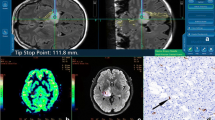

The patient was a 56-year-old male with a contrast-enhancing glioblastoma IDH wild-type located in the left temporal lobe (tumour volume = 137.2 cm3). Perfusion was high (median rCBV ratio = 3.1). Ultrafast Doppler ultrasound showed a highly dense vascular architecture with the superficial cortical vessels exposed (Fig. 5).

Patient #08

The patient was a 46-year-old male with an enhancing grade 4 IDH mutant astrocytoma, located in the right temporal lobe (tumour volume = 113.8 cm3). Perfusion was low (median rCBV ratio = 1.2). Ultrafast Doppler ultrasound reveals exuberant and distorted vasculature (Fig. 6).